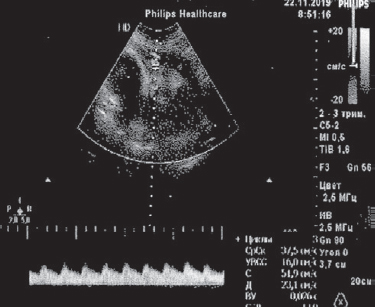

Clinical observation. This article presents the results of observing two women with premature amniotic fluid expulsion at 22 and 24 weeks’ gestation, respectively. In the first case, the woman was immediately admitted to the perinatal center; in the second observation, she was admitted after 3.5 weeks of treatment at another institution. In both cases, pregnant women had manifestations of oligo and endotoxemia, a protective inflammatory response in the mother-placental-fetal system (more pronounced in the second observation) against a background of urogenital infection. In the course of complex treatment, the patients underwent detoxification, of efferent therapy in the form of repeated consecutive sessions of plasmapheresis, hemosorption (one operation each), external photomodification of blood with ultraviolet, laser beams with prolongation of pregnancy by 10 and 8 weeks. The deliveries in both cases were operative with live babies with body weight of 1600 g and 1840 g, respectively. In the first case the infant did not need intensive care, was breastfed, in the second observation the newborn received active respiratory support for 9 days, in the dynamics his condition normalized. No septic complications in mothers and fetuses were observed.